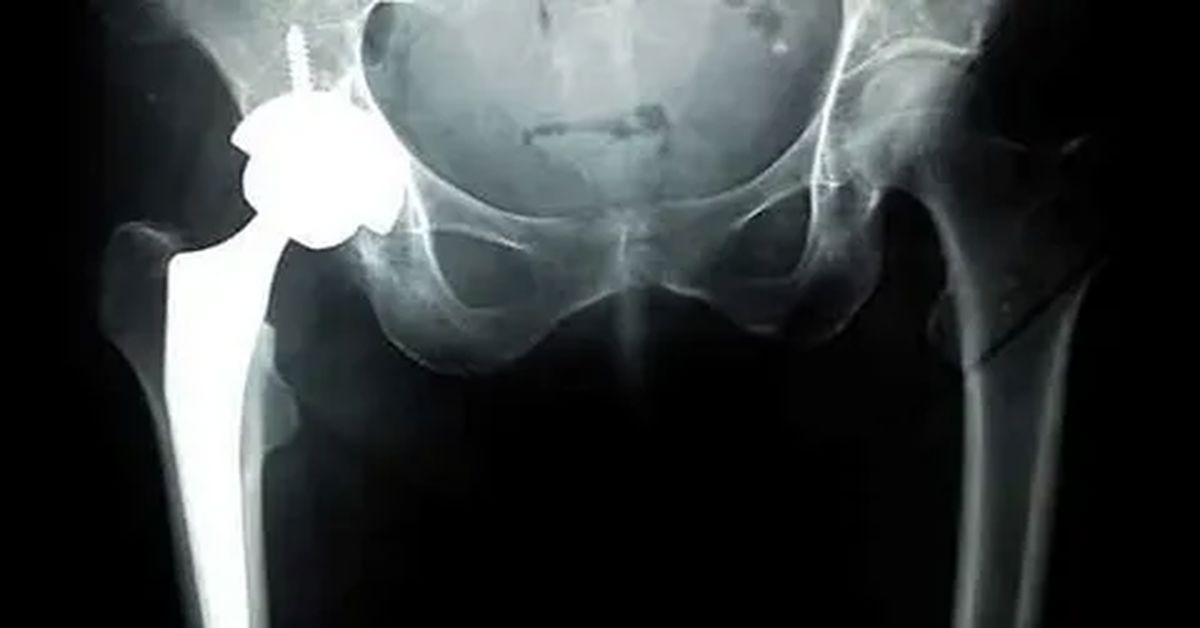

total kalça protezi birinci tür kalça eklemindeki eklem yuvası yapay malzemelerle değiştirilir. Total protezler, eklem deformasyonu olan hastalar için uygundur. Bu sayede hem ağrı azalır hem de eklem hareketliliği önemli ölçüde artar.

Parsiyel protez, sadece hasarlı femur başını değiştirmek amacıyla uygulanır. Genellikle yaşlı hastalarda , ameliyat süresini kısaltır ve iyileşme sürecini hızlandırır. Ayrıca kemik dokusunun büyük kısmı korunmuş olur, bu da uzun vadede avantaj sağlar.

Yüzey replasmanı olarak bilinen bir diğer tür, özellikle genç ve aktif hastalar için uygundur. Bu yöntemde femur başının yüzeyi metal bir kaplama ile değiştirilir, eklem yuvası ise büyük ölçüde korunur. Bu sayede ileride tekrar cerrahiye ihtiyaç duyulma olasılığı azalır ve kemik yapısı korunur.

Farklı protez tasarımları arasında malzeme ve şekil farklılıkları da bulunur. Titanyum, seramik ve özel plastik materyallerden yapılan protezler, uzun ömürlü kullanım ve yüksek dayanıklılık sağlar. Cerrahi sonrası fizik tedavi ile eklem fonksiyonu artırılır ve iyileşme süreci desteklenir.